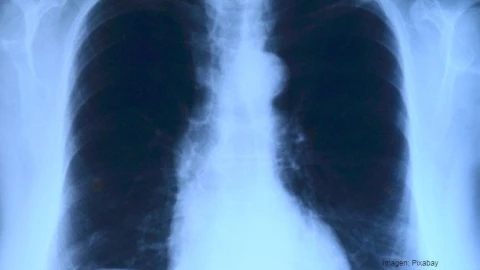

En las radiografías, los médicos distinguieron en el sistema bronquial un objeto metálico ajeno y decidieron actuar inmediatamente.